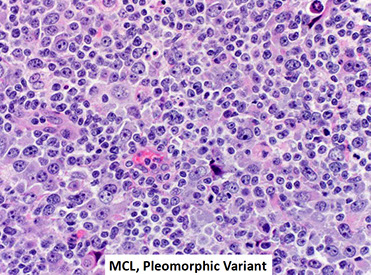

Mantle cell lymphoma (MCL)

- Leukemic non-nodal mantle cell lymphoma

- In situ mantle cell neoplasia (ISMCN)

Naive B cells, which are usually CD5+, are small resting lymphocytes that circulate in PB and are also found in primary lymphoid follicles and follicle mantle zones (aka recirculating B-cells)

- many cases of mantle cell lymphoma thought to correspond to CD5+ naive B-cells